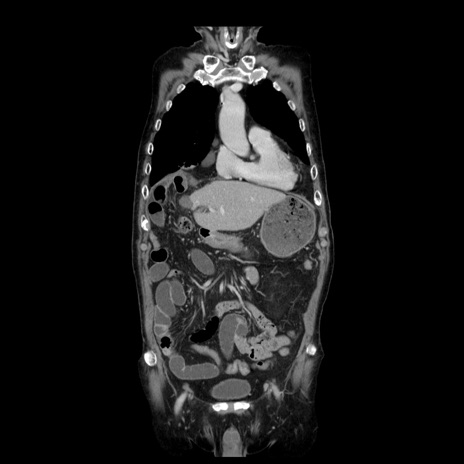

症例21(冠状断像)

【症例】70歳代男性

【主訴】腹痛

【現病歴】肝硬変・肝細胞癌にてかかりつけの方。約9時間前に食後より腹痛出現。症状が徐々に増悪し、嘔吐出現したため来院。

【既往歴】肝硬変、肝細胞癌(RFA、TACE後)

【身体所見】意識清明、表情苦悶様、BT 36℃、BP 129/78mmHg、P 88bpm、SpO2 97%(RA)、右上腹部から心窩部にかけて圧痛あり、反跳痛なし、筋性防御あり。

【データ】WBC 5800、CRP 0.16